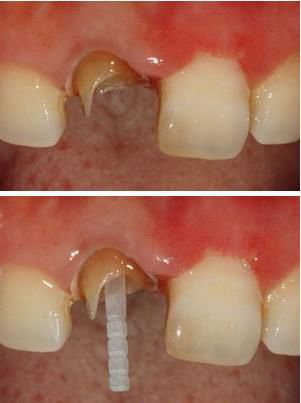

盡可能的多保存牙體組織是大家耳熟能詳?shù)男迯?fù)原則,纖維樁預(yù)備也是同樣如此。但過于薄弱的牙體組織是應(yīng)該去除的,書中給出的標(biāo)準(zhǔn)是牙體組織的厚度要超過1.0mm才能保留,否則決不姑息,一律磨掉。

如下圖剩余的組織就過于薄弱,以后也是一個安全隱患。